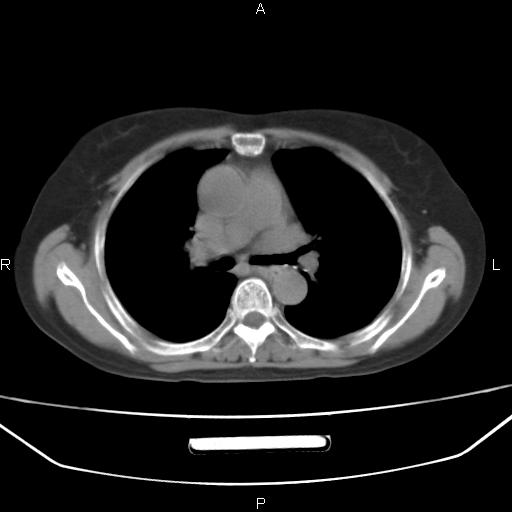

患者,女,66岁。健康体检胸部透视发现右上肺片状阴影。既往无不适,患者自诉三个月前曾有低热病史体温37.5左右一周。用药后缓解。至今无其它不适。请老师们指导指导。

考虑:右肺上叶周围型肺癌(分叶状肿块+砂粒状钙化+胸膜尾征)。

病灶见明显分叶、大小较大(大于3cm?),老年人,多考虑:肺癌,建议穿刺活检。

典型的中心型肺癌,尖段支气管阻塞。

以下是引用dyqct在2010-6-3 9:32:00的发言:[br]考虑:右肺上叶周围型肺癌(分叶状肿块+砂粒状钙化+胸膜尾征)。

不像中央型啊

周围性肺癌,

右肺上叶周围型肺癌可能性大。

考虑:右肺上叶周围型肺癌